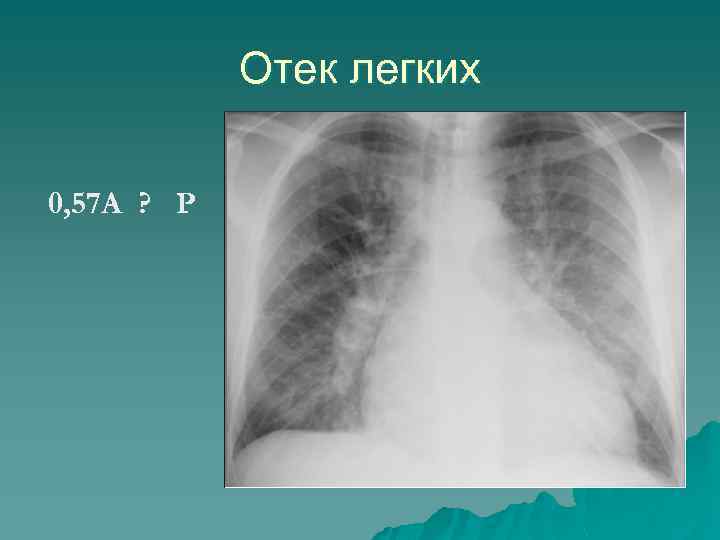

Гипоксемия «Белая» рентгенограмма Отек легких ОРДС Вирусная пневмония Жировая эмболия Пневмония Ателектазы «Черная» рентгенограмма Обострение ХОБЛ ТЭЛА Микроателектазы

Отек легких 0, 57 A ? P